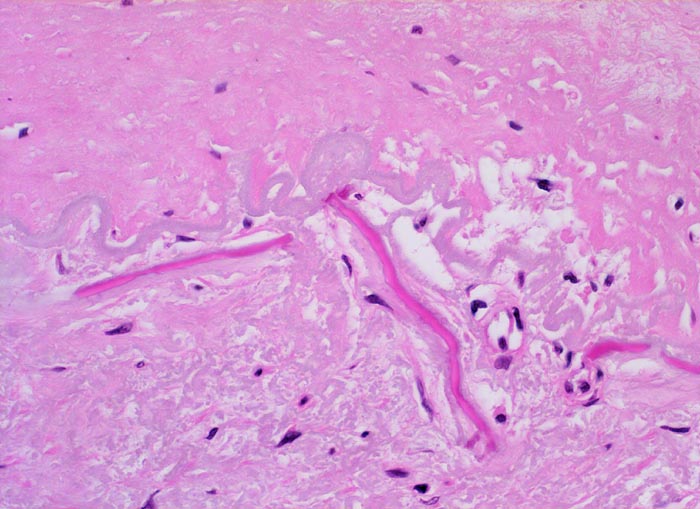

Atherosklerose

Arteria poplitea

Aufgesplitterte Lamina elastica interna zwischen sklerosierter Intima oben im Bild und atropher Media unten im Bild. Einzelne Fasersplitter sind verkalkt.

Patient mit arterieller Hypertonie und 42 Pack Years Nikotinabusus. Klinisch PAVK IIa mit gelegentlichen leichten Schmerzen im rechten Bein nach längeren Gehstrecken.

Histologie

400